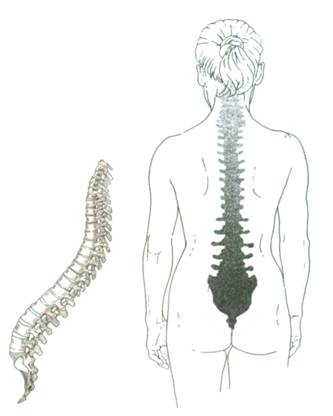

О том, что позвоночник – самая важная поддерживающая и опорная конструкция всего организма, известно каждому жителю планеты. Но, поскольку он находится внутри тела, да еще и сзади, не на виду, многие забывают о его существовании, или считают крепость и исправность этой конструкции само собой разумеющейся. Ежедневно на позвоночный столб оказывается давление, практически постоянно. За счет него мы передвигаемся, ходим на выпрямленных ногах без помощи рук. Природа позаботилась о том, чтобы позвоночник был достаточно гибок, имел упругую структуру, способную в нужный момент самортизировать и смягчить деформации, которые неизбежно возникнут при сильных нагрузках. Но человек порой делает все, чтобы усложнить позвоночнику задачу по прямохождению и поддержанию центра тяжести. И только когда начинаются проблемы, он вспоминает о позвоночнике и начинает интересоваться: почему спина болит, как все устроено, из чего состоит и как работает.

Позвоночная дуга называется так, поскольку имеет изогнутую форму, помогающую быть органу упругим и гибким. Без позвоночника невозможно себе представить жизнь человека, поскольку при его отсутствии (или если позвоночник поврежден) он не сможет не только ходить прямо, но даже просто стоять. Получается, что от состояния этого органа зависит не только здоровье, но и жизнедеятельность.

Центральная ось скелета, позвоночник, формируется 24 позвонками, крестцом и копчиком. Он содержит спинной мозг и спинномозговые нервы. Он связан с тремя блоками: головой, грудной клеткой и тазом, и содержит зоны, которые образуют три последовательных изгиба, видимых в профиль.